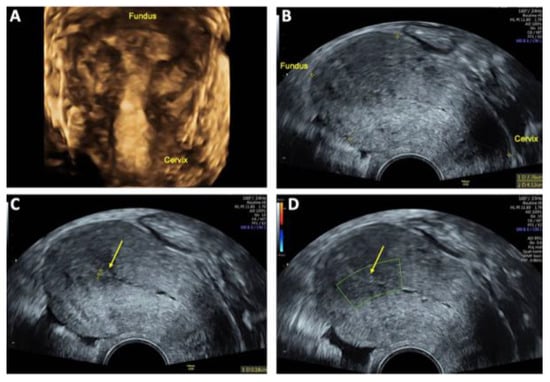

At the 12-week follow-up, ultrasound examination showed no residual evidence of the previously detected uterine AVM. The endometrial thickness measured 2 mm with no abnormal vascularity (Figure 7). The patient reported having a regular menstrual cycle without abnormal pain or discomfort, suggesting complete resolution of the AVM and a successful treatment outcome.

Figure 7. Follow-up transvaginal sonography (TVS) at 6 and 12 weeks after uterine arteriovenous malformation (AVM) embolization: (A) 3D TVS at 6 weeks showing no evidence of a lesion within the uterus cavity; (B) 2D TVS after 12 weeks demonstrating an almost normal sized retroflected uterus measuring 78 × 41 mm; (C) 2D TVS after 12 weeks showing a smooth endometrium with a thickness of 2 mm (arrow); (D) 2D TVS after 12 weeks confirming no abnormal perfusion within in the uterine cavity (arrow), indicating successful resolution of the AVM.